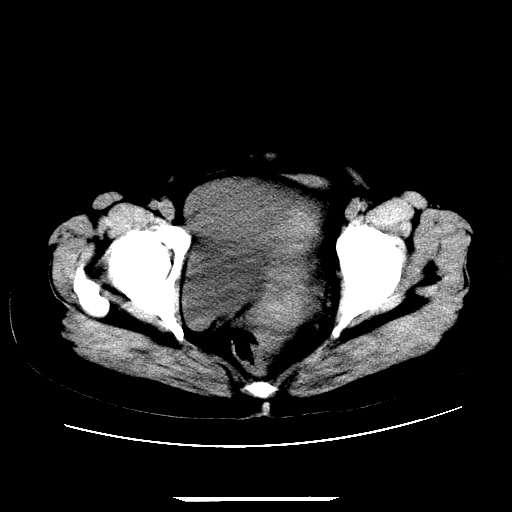

f,45y.怀孕4月晕倒,b超提示死胎,有手术结果,请展开讨论后明天告诉。

膈下-肠间隙内见气体密度影,子宫轮廓显示不清,宫腔-腹腔积液,首选考虑---子宫破裂出血。

1)宫腔妊娠。2)子宫破裂出血,腹腔及盆腔积血。

感谢同行们的高见。手术结果:子宫破裂出血。

我们的诊断是:腹、盆腔积液(考虑腹盆腔脏器破裂出血);宫腔妊娠。让人纳闷的是当时我们没有经验,现在回头看看分析:4月宫腔妊娠:1、洋膜囊不可能紧贴胎体这么小;2仔细看看子宫后壁肌层模糊不清;3腹、盆腔液体来源原因?4、45岁高龄妊娠有晕倒。由此可大胆诊断:宫腔妊娠子宫破裂出血。